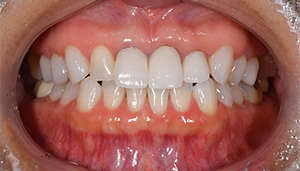

症例3

治療前

治療後

治療内容

ホワイトニングを行い、歯が白くなり、被せ物の色が周りと合わなくなったので、前歯3本の被せ物を変更しました。

治療期間 1ヶ月

治療費 合計:495,000円

(内訳)

ジルコニアボンド:165,000円×3本

治療のリスク・副作用 被せ物を外すと、ご自身の歯が少ない場合は別途はを残すための処置が必要になることがあります。

歯のホワイトニング